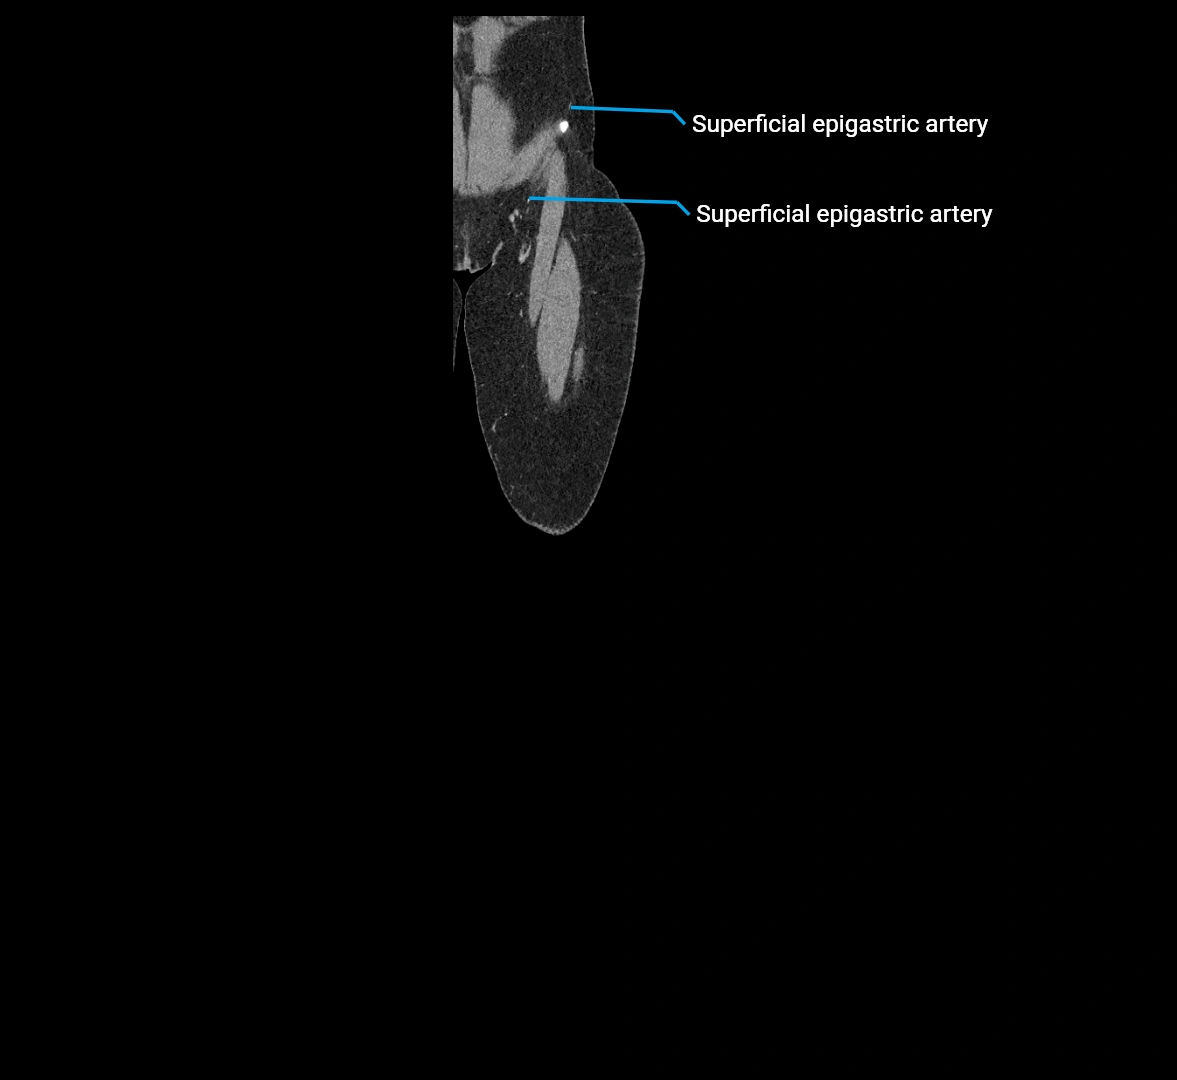

CT images

image

Contrast-enhanced CT (CTA):

• Gold standard for abdominal aortic imaging

• Provides excellent detail of lumen, wall, aneurysm, thrombus, and branch vessels

• Multiplanar and 3D reconstructions help in aneurysm measurement, stent graft planning, and dissection evaluation